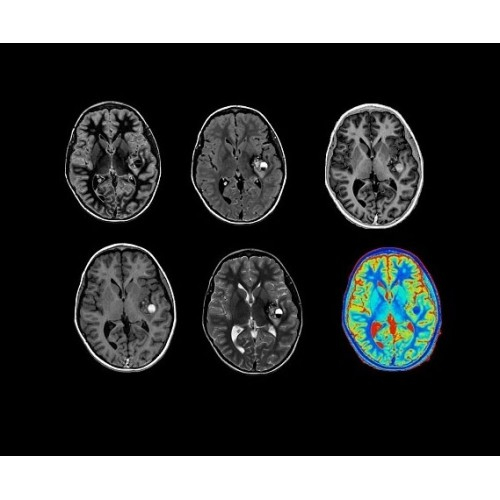

SIGNA Architect 3.0T — это новейший МРТ аппарат компании GE, который предлагает высочайший уровень производительности — в системе 128 приемных каналов, 48 канальная катушка головы, полный спектр клинических возможностей. Высокий уровень комфорта пациента обеспечивают такие особенности как отсоединяемый стол, положение пациента «ногами вперед» для всех видов исследований, SilentWorks — бесшумное и MAGIC — быстрое сканирование.

Теперь возможности МРТ поражают еще больше благодаря ультрасовременным решениям для визуализации с SIGNA Architect 3.0 Тл, объединяющей новейшие достижения в области МР-технологий и интуитивно понятный интерфейс. Система SIGNA Architect, разработанная на базе новой платформы SIGNA Works, представляет собой гармоничное сочетание дизайна и функциональности. Каждый элемент системы направлен на повышение производительности, эффективности клинической практики, финансовых показателей, а также комфорта и безопасности пациента.

Поле обзора 50x50x50 см и апертура шириной 70 см позволят достоверно визуализировать сложные анатомические области для пациентов с крупным телосложением, например, плечи и бедра. Феноменальная однородность системы SIGNA Architect обеспечивает наиболее широкое поле обзора с улучшенными характеристиками градиентов. Ничто не останется незамеченным.

• NeuroWorks — универсальное решение для визуализации анатомии головного мозга, позвоночника, сосудов и периферических нервов с четкой дифференциацией тканей.

• 48-канальная катушка TDI для головы, входящая в базовую комплектацию SIGNA Architect, обеспечивает феноменальную производительность с учетом особенностей каждого пациента. Благодаря гибкому и универсальному дизайну, высокому соотношению сигнал/шум и передовым технологиям визуализации, таким как HyperWorks, учитываются потребности подавляющего большинства пациентов.